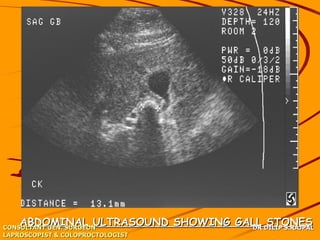

ABDOMINAL ULTRASOUND SHOWING GALL DILIP S.RAJPAL

STONES